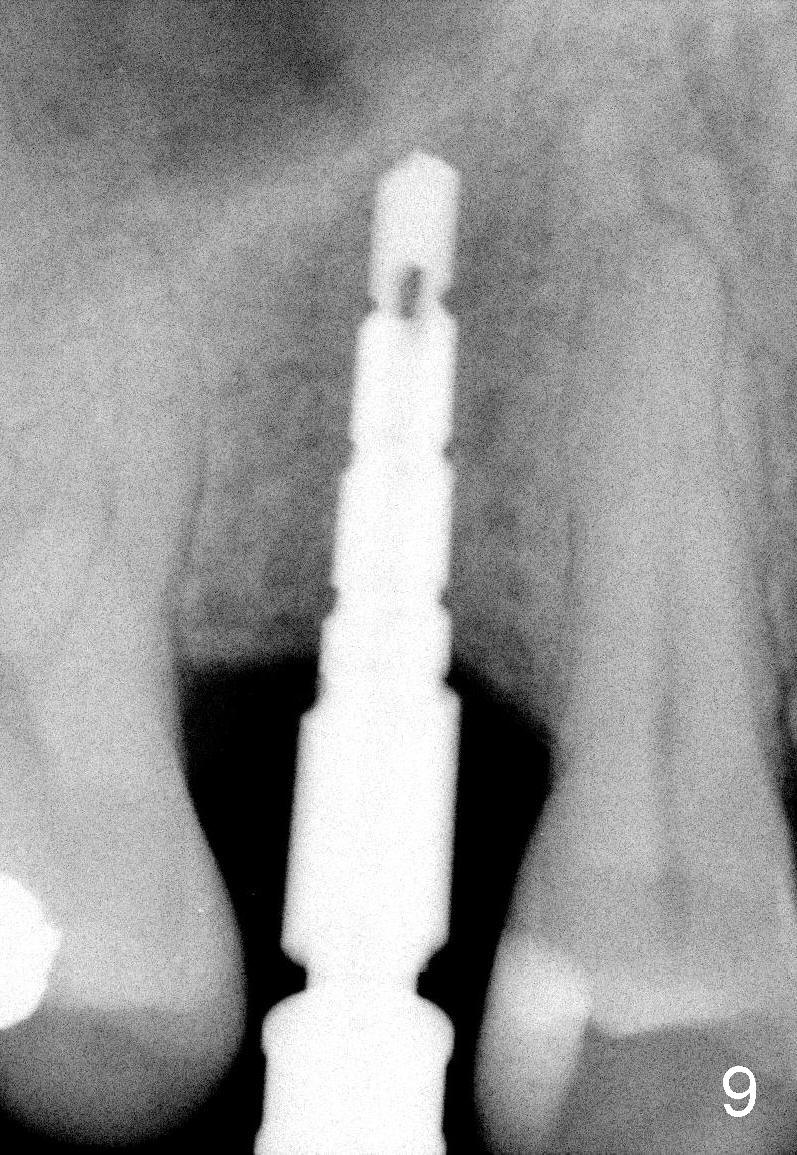

Nine months later, the patient returned for re-implantation (Fig.7). Amoxicillin and Chlorhexidine were used preop and postop. Flaps were raised for better vision of reimplantation site (Fig.8). Bone density was high (type II). Drills were used to form osteotomy (Fig.9). A 4x17 mm implant was placed with internal sinus lift (Fig.10*). The insertion torque was also >60 Ncm. The flaps were approximated and a short abutment (Fig.11 A) was placed to hold perio dressing in place.